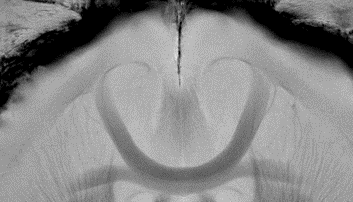

The BioSpec 180/11 is the ultimate in ultra-high-field MR imaging with unparalleled sensitivity for greatest resolution. Its streamlined design for mice studies makes handling simple, while its powerful software guarantees best results. It can be equipped with the MRI CryoProbe to increase sensitivity even further and together with the gradient strength of up to 1000 mT/m, highest resolution is achieved. It is built with Ultra Shielded and Refrigerated (USR) magnet technology for reduced maintenance costs and longer service intervals.

• Crisp and highly resolved images with native gradient strength of 740 mT/m, upgradable to 1000 mT/m

• MRI CryoProbe for exceptional increase in sensitivity